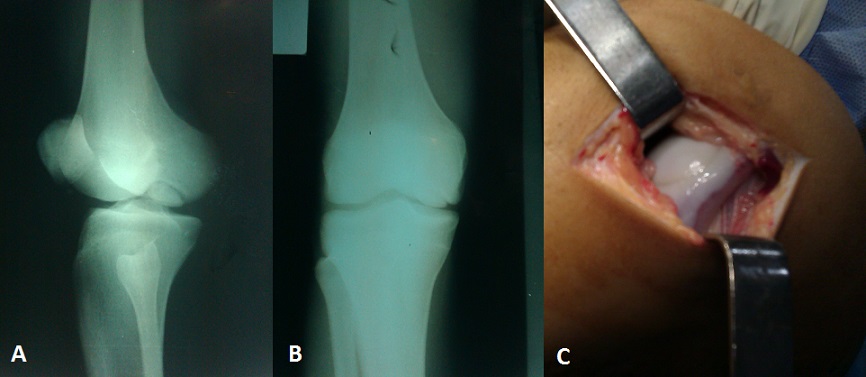

L'Ostéochondrite disséquante des condyles fémoraux est une affection rare. Elle se définit comme une zone localisée de modifications vasculaires atteignant l'os sous chondral. La physiopathologie n'est pas connue mais l'hypothèse mécanique et vasculaire reste au premier plan. La classification de Bedouelle permet une analyse précise de la lésion et a un intérêt dans l'indication thérapeutique. La symptomatologie est dominée par la douleur mécanique du genou, rarement une sensation d'accrochage ou de blocage lorsque le fragment est libre en intra articulaire. Le diagnostic est radiologique. L'arthroscanner a pour intérêt l'étude de la stabilité du fragment. L'IRM et la scintigraphie permettent l'étude de sa vitalité. Les techniques chirurgicales sont multiples et peuvent aller de la simple fixation du fragment jusqu'à des techniques de reconstructions cartilagineuses lorsque le fragment n'est pas viable et le défect cartilagineux est important. Le pronostic à long terme est dominé par la survenu d'une arthrose pouvant nécessiter la mise en place d'une prothèse totale du genou.